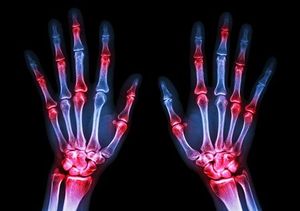

Patients with rheumatoid arthritis who had inadequate response to previous biologic disease-modifying antirheumatic drugs found greater pain relief when taking 2 mg or 4 mg of baricitinib compared with placebo.